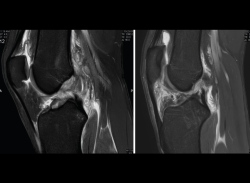

4.3. Osteocondritis

En la osteocondritis se aprecia una lesión subcondral caracterizada por resorción ósea, colapso y la formación de un secuestro.

El estudio por RM es una herramienta valiosa para diagnosticar e identificar las lesiones del cartílago. Conocer el aspecto del cartílago y saber cuánto y cuándo se lesiona, basándose en las clasificaciones actuales, permiten al radiólogo proporcionar la máxima información al clínico(20).

Figura 53. Corte de secuencia sagital (A) y axial (B) T2 Fat-Sat de RM de rodilla: lesiones osteocondrales en el fémur y la rótula.

Numerosos estudios demuestran la utilidad de la RM para definir la estabilidad o inestabilidad de la lesión en la osteocondritis, destacando su carácter no invasivo y la capacidad de valorar la progresión y la respuesta al tratamiento(21)(Figuras 53 y 54).

Figura 54. Corte de secuencia T1 y T2 Fat-Sat coronal de resonancia magnética: gran osteocondritis en el cóndilo femoral interno con edema en la medular adyacente.